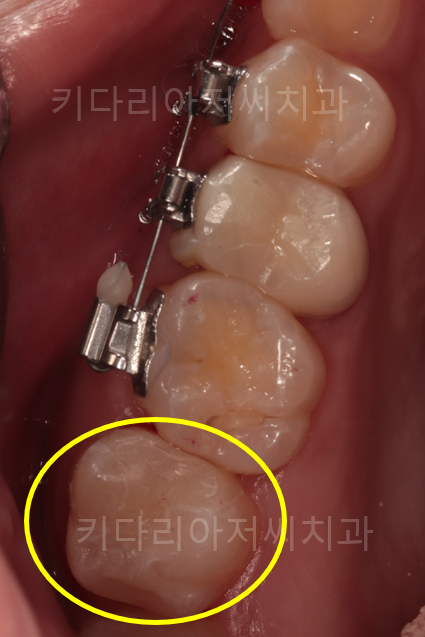

오른쪽 아래 소구치, 대구치 치료 전후 사진입니다.

충치의 범위가 넓기 때문에 레진으로는 치료를 할 수가 없어 하이브리드 인레이(부분보철)로 진행을 했어요.

치료 후 완벽하게 수복하여 치아 내부를 보호하고 있는 모습을 볼 수 있습니다.